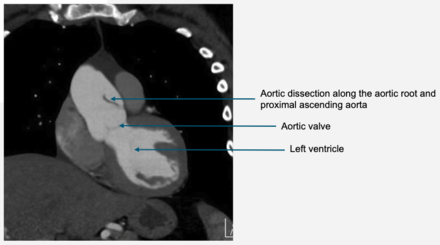

A 26 yo woman with Marfan Syndrome (MFS, FBN1), ectopia lentis, aortic dilation and no family history of MFS or aortic dissection was evaluated for preconception counseling. She was asymptomatic, and the size of her aortic root (~4cm) and ascending aorta (~3.5cm) had been stable for over 5 years. She was counseled that risk of cardiac events during her pregnancy is high, but lower compared to those with aortic sizes >4.5cm. Once pregnant, she was followed closely with imaging every trimester (MRA at 25 weeks gestation showed stable aortic sizes). Cardio-obstetric recommendations included: CARPREG II score: 2, mWHO class: III, consideration of assisted second stage due to aortic root dilation. She was counseled on symptoms of aortic dissection and to seek emergency care should those symptoms arise. At 27 weeks gestation, she presented to the ED with intense chest and neck pain, shortness of breath, and headache. Emergent CT showed aortic root (4.1cm) and proximal ascending aortic dissection with propagation into the left main coronary artery (Figure 1). She underwent emergent C-section followed by aortic root and ascending aorta replacement and mechanical aortic valve replacement due to severe regurgitation. She was discharged in stable condition 8 days after an uncomplicated post-operative recovery. Her baby is recovering in the NICU.